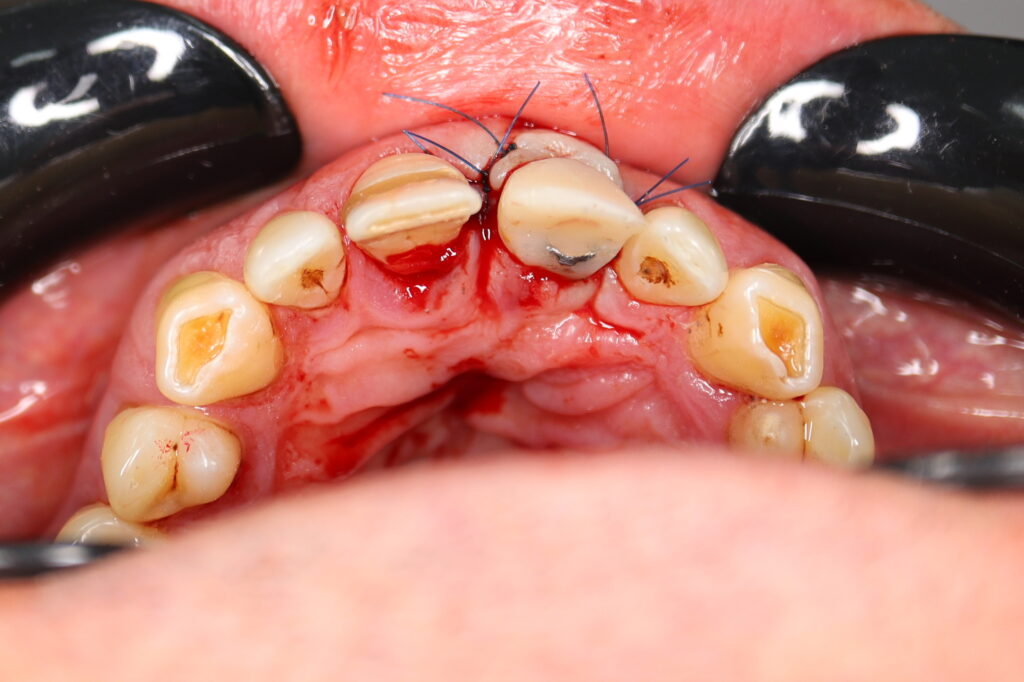

Процесс работы

Что было сделано:

Лечение состояло из двух этапов: хирургический и ортопедический. Длилось 4 месяца.

Были установлены 4 имплантата Straumann BLT. На верхней челюсти в области зуба 2.1 в одно посещение был установлен имплантат и изготовлена временная коронка.

Также в данной области выполнена пластика десны.

хирургический этап

Это фото может содержать тяжелый для восприятия контент

Результаты хирургического этапа